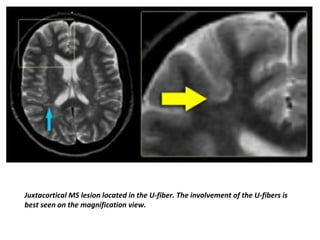

Juxtacortical MS lesion located in the U-fiber. The involvement of the U-fibers is

best seen on the magnification view.